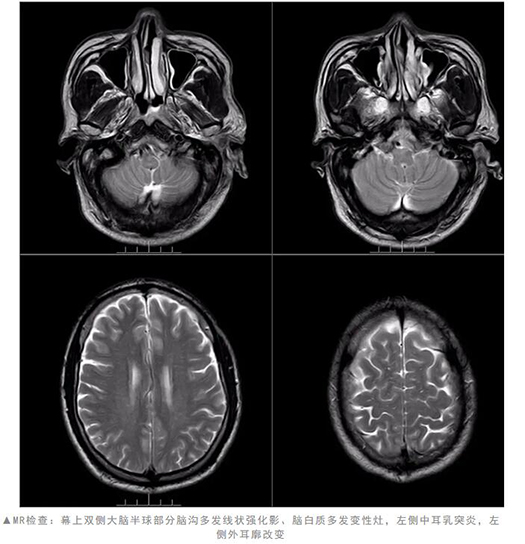

为明确诊断,在王展航指导下,神经内一科主管医生周丽华为患者安排了相关检查。结合症状及检查结果,赵叔的确是感染了疱疹病毒,被明确诊断为亨特氏综合征。